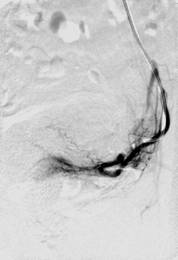

Bei der interventionellen Therapie erfolgt durch Embolisation (Einschwemmung von kleinen Kunstpartikeln) die Verödung von Myomen. Dazu wird nach örtlicher Betäubung durch einen Radiologen ein Katheter in die Leistenarterie eingebracht, über den winzige Kügelchen in das Myom eingeschwemmt werden, die dafür sorgen, das die Blutzufuhr zum Myom unterbunden wird. Innerhalb von drei bis sechs Monaten schrumpfen die Myome bis auf ca. die Hälfte ihrer Ausgangsgröße. Diese Methode kann also vorteilhaft für Frauen sein, deren Familienplanung zwar abgeschlossen ist, die aber einen Organerhalt wünschen.